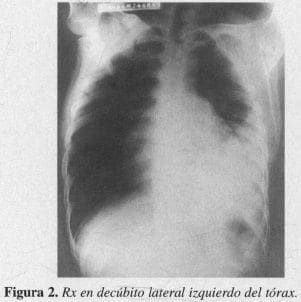

Reingresa el 12-X-96 (13 días después) con dolor en el hemitórax izquierdo, disnea de medianos esfuerzos y ascenso térmico no cuantificado; clínicamente persistía matidez basal izquierda, ingurgitación yugular a 45º. Los Rx mostraron colección que no se desplazaba en el decúbito la-teral izquierdo; cardiomegalia Grado I-II y rectificación de los contornos de la silueta cardíaca con pérdida de su escotadura (Figuras 1 y 2). Se tomó ecocardiograma que mostró hemopericardio anterior y posterior de 200 a 300 mL, con signos de taponamiento como colapso sistólico de la aurícula derecha con ausencia de colapso de la vena cava inferior durante la respiración. Función ventricular izquierda normal.